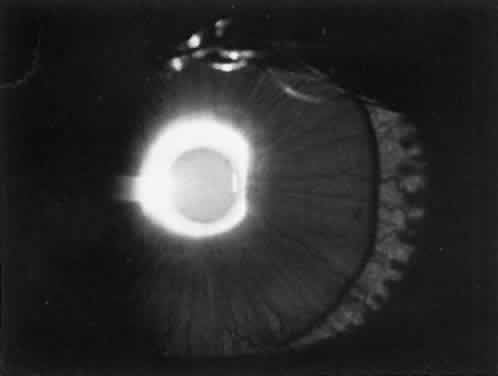

The lens in homocystinuria is much more mobile than in the Marfan syndrome. This may be related to the clinical observation of progressive irregularity of the zonular fibers and the appearance of a fringe of white zonular remnants at the equator of the lens and on the surface of the ciliary body (Fig. 1).12,13 Henkind and Ashton first reported histopathologically the ocular findings in four eyes of three homocystinuric patients. They found the zonular fibers to be deficient adjacent to the lens. These zonules had recoiled to the surface of the ciliary body and were matted and retracted into a feltwork that fused with a greatly thickened basement membrane of the nonpigmented epithelium. The greatly thickened basement membrane overlying the ciliary body in homocystinuria has subsequently been shown by electron microscopy to be composed of degenerate zonular material.14 In addition, Ramsey and coworkers noted that the degree of zonular abnormality was related to age: the younger the patient, the more normal-appearing zonular fragments composed of oriented filaments that could be identified.14 The zonular fibers are composed of glycoproteins with a high concentration of cysteine, which may explain their susceptibility to abnormal function in homocystinuria.15,16